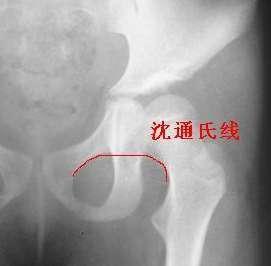

沈通氏线(Shenton’s线):是指正常骨盆X线中耻骨下缘弧形线与股骨颈内侧弧形线连成的弧度。

关节脱位:外伤性(常合并撕脱性骨折、韧带或软组织损伤。分为完全/半脱位);

非外伤性(先天性髋关节脱位)